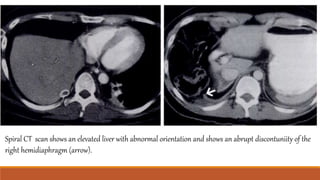

Spiral CT scan shows an elevated liver with abnormal orientation and shows an abrupt discontuniity of the

right hemidiaphragm (arrow).